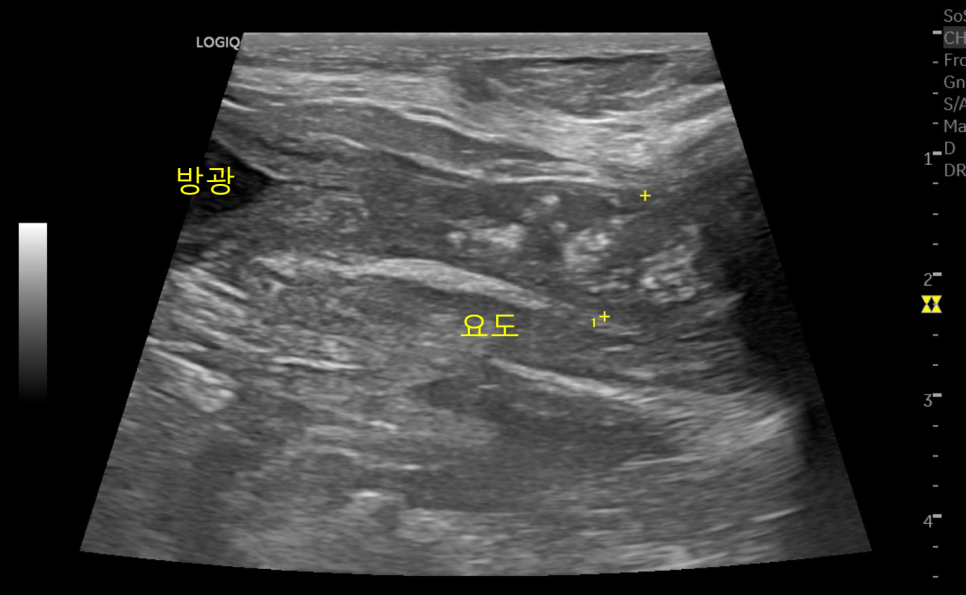

강아지 요도벽의 비후 및 종양성 변화와 석회화

강아지 환자는 CT검사 결과로부터 하부 요로계 (방광/요도) 종양을 의심하게 되었고, 조직검사를 통한 확진이 필요한 상황이었습니다. 보호자님과 상담 후 방광경을 이용한 비침습적인 방법으로 조직검사를 진행하기로 하였습니다.